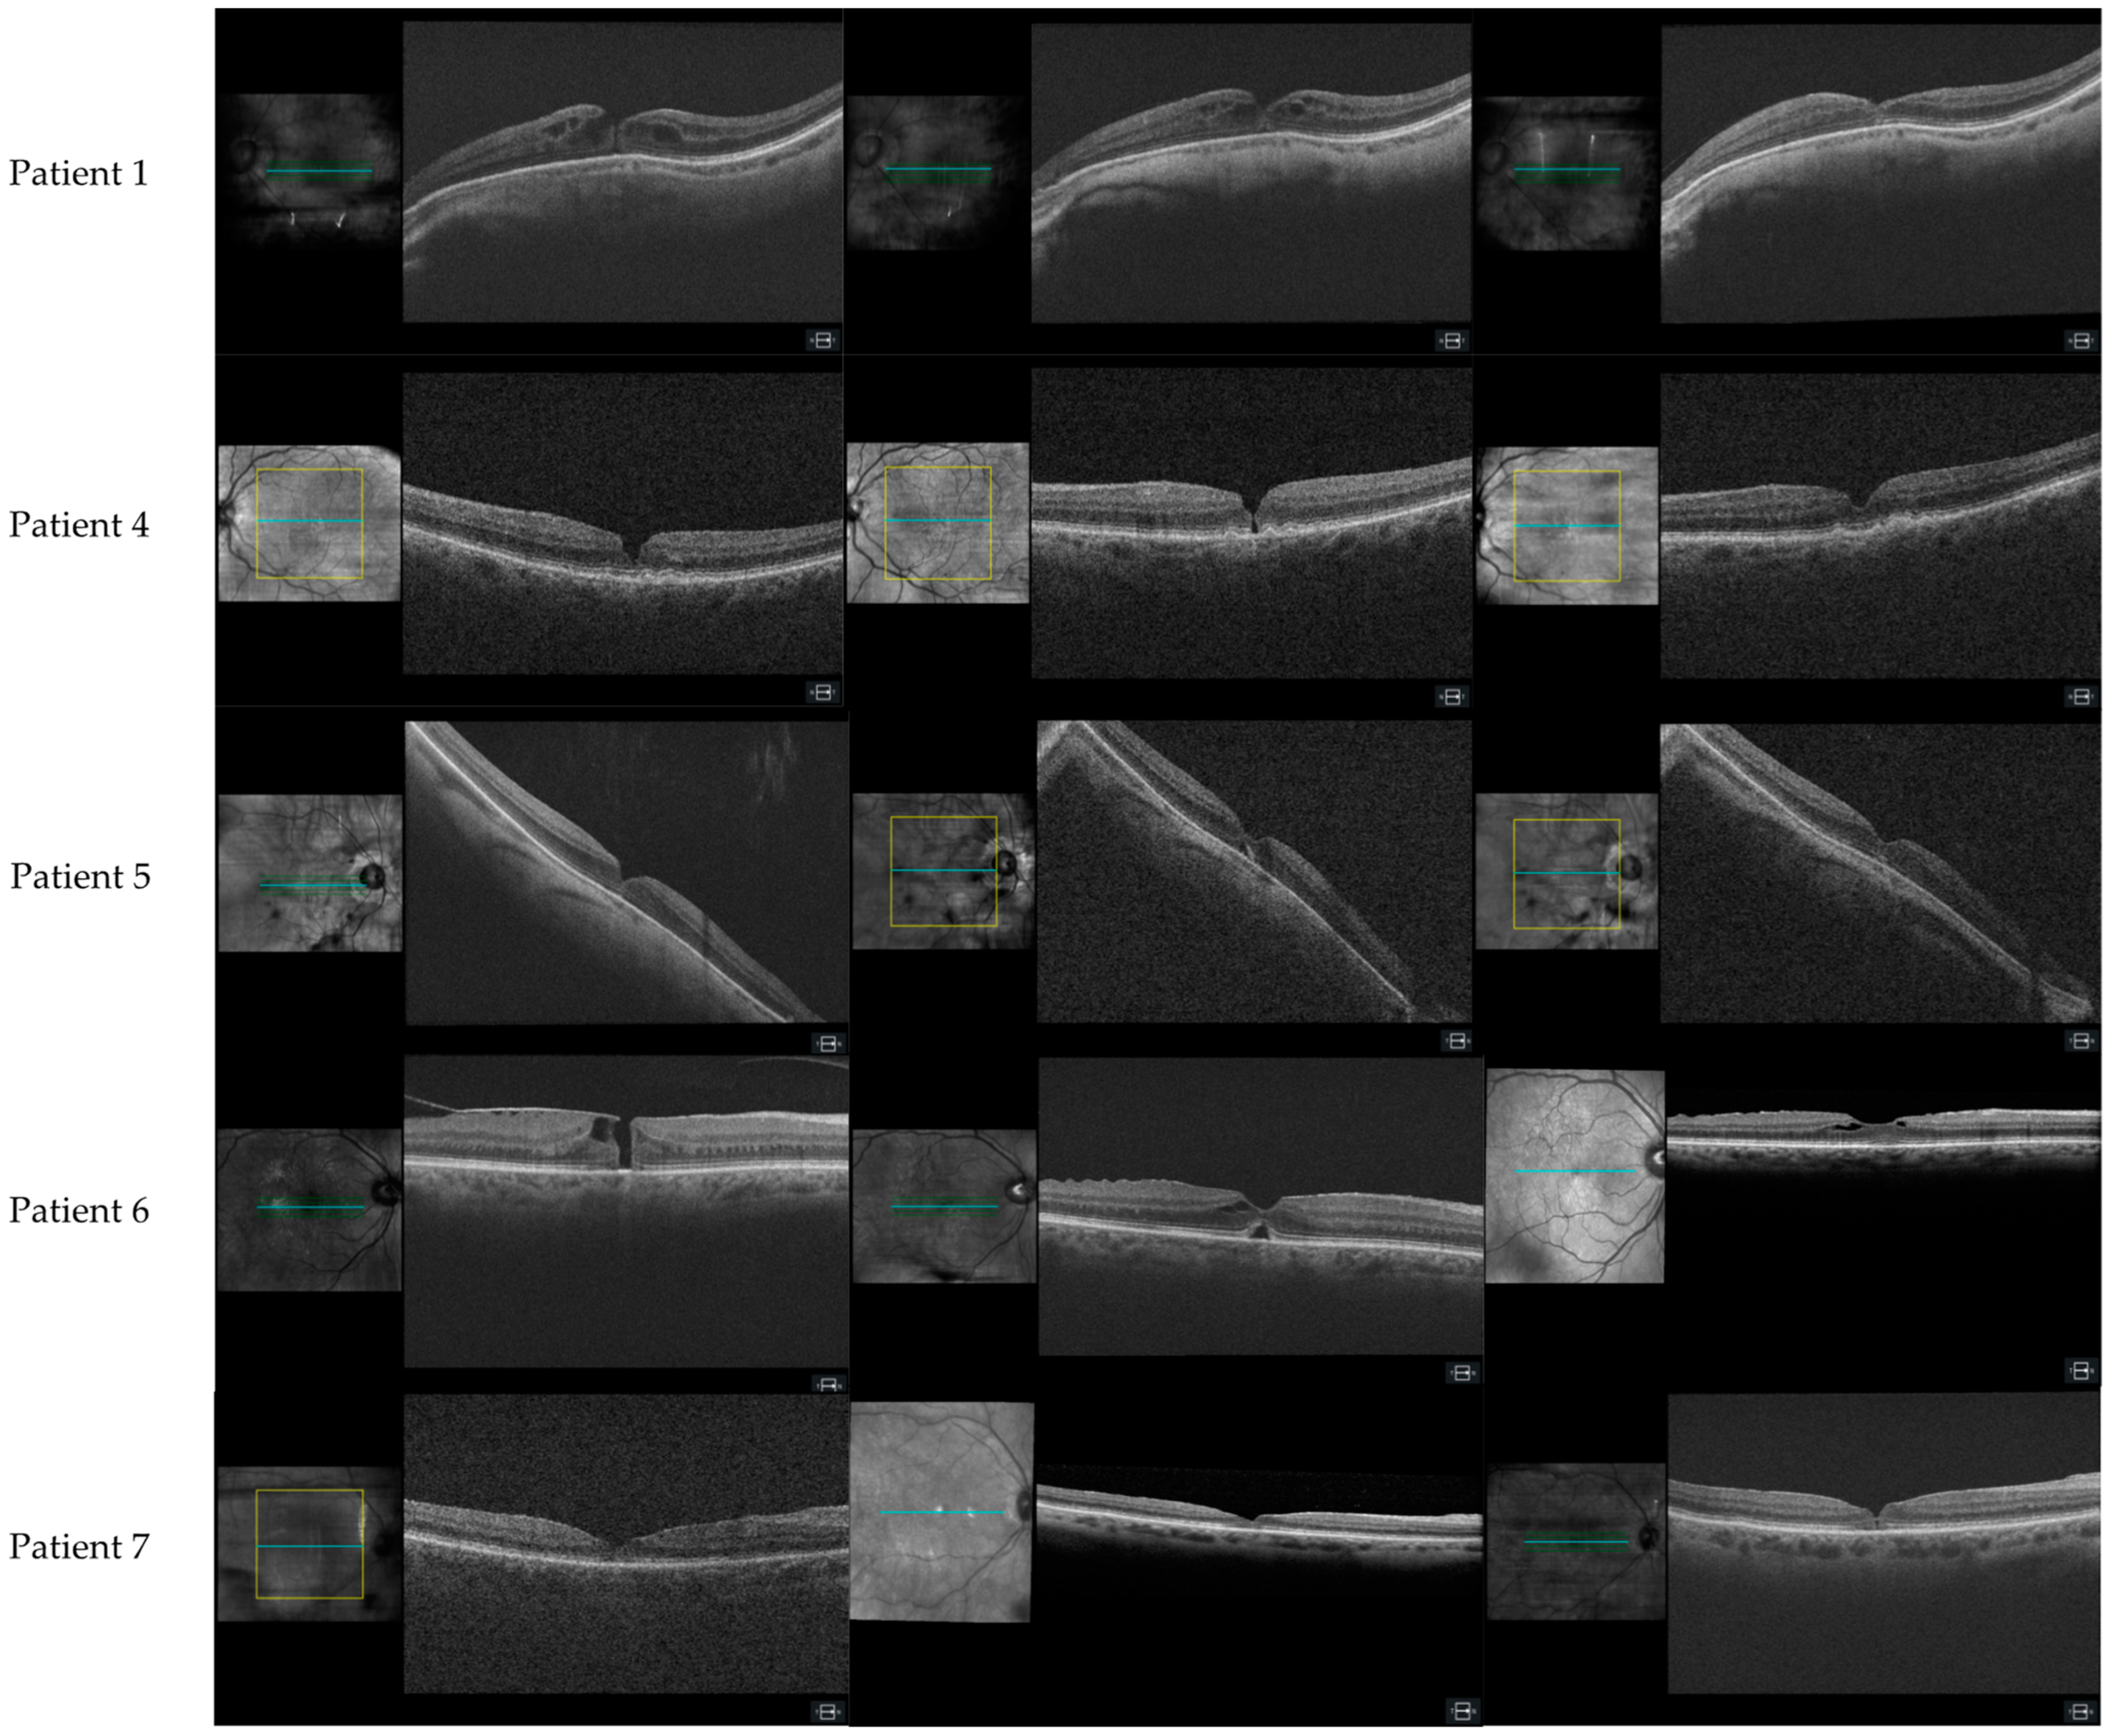

3.1.1. Patient 1, Left Eye

3.1.4. Patient 4, Left Eye

3.1.5. Patient 5, Right Eye

3.1.6. Patient 6, Right Eye

3.1.7. Patient 7, Right Eye